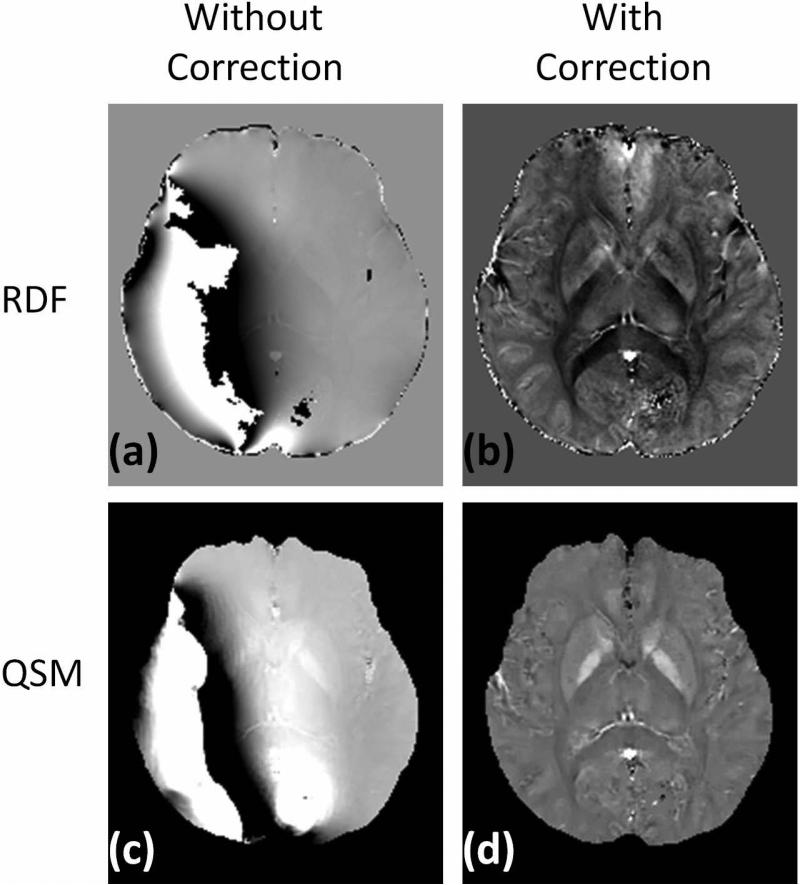

All the spatial positions between the repeated acquisitions matched remarkably well (mean translations: 0.16±0.10 mm; mean rotations: 0.20±0.19 degrees), so registration was not performed before calculating the noise. The noise measurements are summarized in Fig. 5. The use of bipolar multiecho acquisition leads to a statistically significant noise reduction for all subjects and all ROIs (P<0.0001). On average, this noise reduction ranges from 18.0% for the caudate nucleus to 31.2% for substantia nigra. Figure 6 shows the local field map and quantitative susceptibility map of one case acquired with bipolar 12 echoes and reconstructed without or with correction of the phase shift of even echoes. The reconstruction failed to obtain correct local field map and consequent quantitative susceptibility map in this case if the echoes were combined naively, i.e. without accounting for the phase shifts (Fig.6a&c).

Fig. 6.

The local field maps (top row) and quantitative susceptibility maps (bottom row) of one case acquired with bipolar 12 echoes and reconstructed without (left column) or with (right column) correction of the phase shift of even echoes.

Gradient delays and eddy currents caused by the rapidly changing gradient field may induce phase changes in all spatial directions [38]. The odd-even-echo phase discrepancies are fairly constant along the phase (ky) encoding directions and can be explained by the gradient waveforms changing very little among different ky encodings. The linear phase error in the readout and slice-selection directions is the dominant component seen in the bipolar multiecho acquisitions, which can be explained as the effects of both gradient delays and stronger eddy currents in the readout and slice-selection directions. The linearity offers a simple and robust correction for phase discrepancies. It is possible to fail to obtain correct local field maps and quantitative susceptibility maps if the echoes were combined naively, i.e. without accounting for the phase shifts.